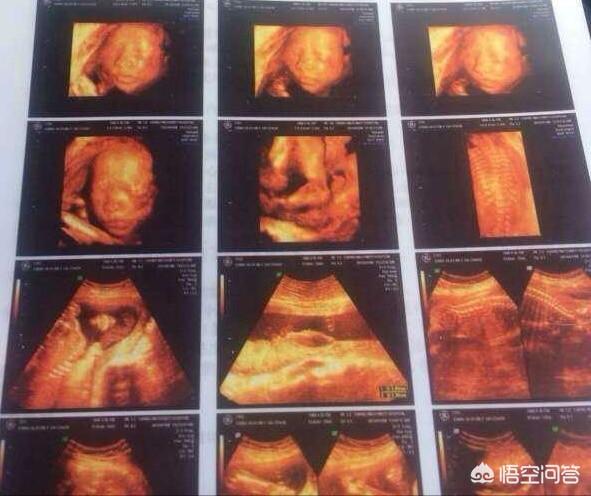

妊娠後、人の心はより敏感になり、荒唐無稽なことを考えたがるようになる。超音波検査の医師が、胎児は足が長いと言ったとき、赤ちゃんに何か問題があると思わないでください。 胎児は発育が良く、足が長く育つ可能性があると言っているのかもしれません。

生後8ヶ月の4D超音波検査では、赤ちゃんの状態を、指や足の指のような小さな関節まではっきりと見ることができます。胎児に少しでも問題があれば、超音波検査医はその可能性を知らせる義務があります。赤ちゃんの足が長い」というのは単なる冗談かもしれませんが、医師は冗談のように問題を伝えるのではなく、本当に問題がある場合はすぐに伝えます。